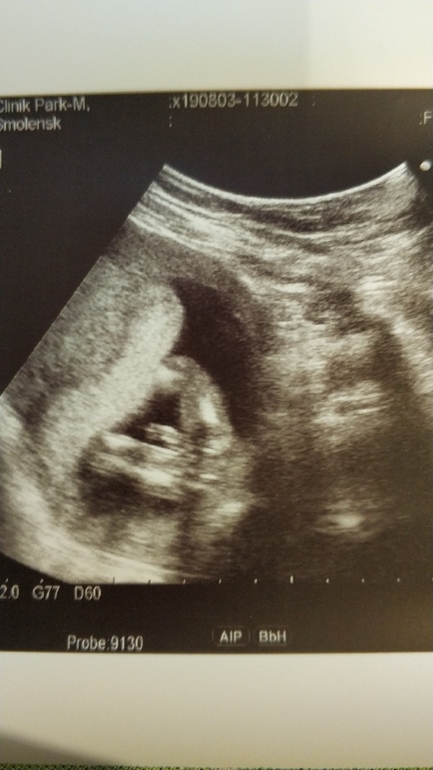

Пол малыша, часть вторая)))

Это мальчик 😃у нас так же было😃

16 вроде😃

Явно мальчуган:)

Это мальчик, чего тут сомневаться🤷‍♀️

Конечно мальчик!

Мальчик

Мальчик!))